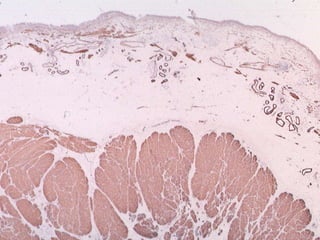

Fatores de Risco – T1 Alto GrauPresença de Ca in situ (CIS)Acometimento de uretra prostática ou ureter distalMultifocalidadeTamanho > 3 cm (imagem)Profundidade de infiltração na lâmina própria (T1B)Invasão linfovascularTumor em divertículo vesical

Fatores de Risco– T1 Alto GrauPresença de Ca in situ (CIS)Acometimento de uretra prostática ou ureter distalMultifocalidadeTamanho > 3 cm (imagem)Profundidade de infiltração na lâmina própria (T1B)Invasão linfovascularTumor em divertículo vesical